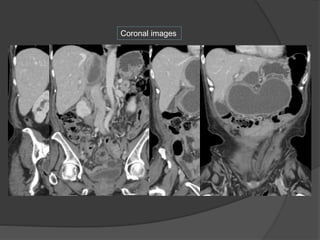

Coronal images

Case 1: 38 M with acute onset severe abdominal

pain

Cecum in the lesser sac

Diagnosis?

Cecum mildly dilatedCecum in the lesser sac between

the liver hilum and IVC

No twist to indicate cecal volvulus

Case 1 Diagnosis: Lesser sac hernia with cecal

incarceration

 Cecum large and distended

within the lesser sac

 Cecum and bowel viable

 Cecum and ascending colon

extremely mobile with no

lateral attachments

 Right colectomy done to

prevent recurrence

Surgery:

Case 7: 38 M with acute onset severe abdominal pain

Dx: Lesser sac hernia with cecal incarceration

Take home points-

1. Look for abnormal location of a bowel loop indicating an internal

hernia

2. Abnormal dilatation of the abnormally located loop may indicate

3. Absence of beak sign or mesenteric twist can exclude volvulus

Lesser sac hernia via the foramen of

Winslow